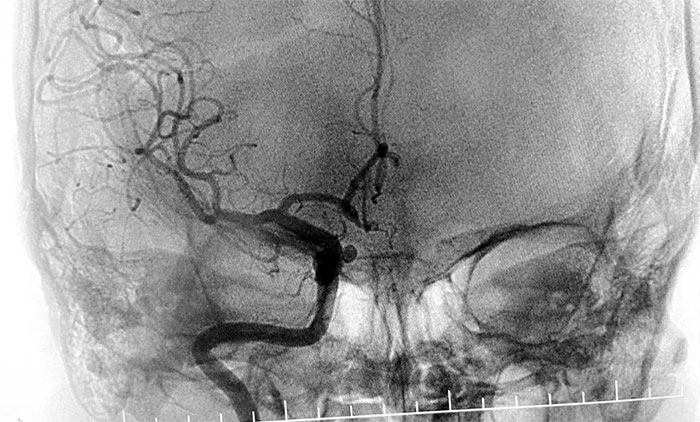

4旬男子头痛抽搐确诊静脉窦血栓 席刚明教授团队介入取栓及时打通生命线

近日,上海蓝十字脑科医院学术副院长、神经内科4A病区主任席刚明教授带领团队迎难而上,及时为一位静脉窦血栓患者行介入取栓治疗,顺利打通生命线,挽救了患者生命,也标志着上海蓝十字脑科医院神经介入诊...【详细】